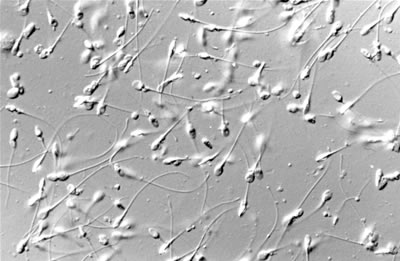

RESULTADOS SEMINOGRAMA

Resultado: Concentracion espermática 0.5Mill/mL, Recuento total espermatozoides 2,3. Millones, Motilidad progresiva 5% y espermatozoides inmoviles 95%. A mi entender muuuyy xdebajo.La Gine mea dicho que tome auxina A+E, haga yoga, y busque en internet comidas que favorezcan la movilidad..y repetir en 3 meses. Cuantos cp de Auxina tiene qtomar pq la gine no lo sabia(mea dicho qloq ponga enel prospecto pero en el prospecto pone de 1 a 3) y que otra cosa podría tomar?.Aconseja auxina forte? Agradecería que nos ayudaran pq la Gine no tenía mucha idea…considero que este tipo de ayuda va bien cd son cifras un poco xdebajo pero esto…en fin…comentarme que mas puede tomar y sino en 3 meses volveremos a ver que nos dicen. Muchas gracias. Eli

El resultado de seminograma que me presentas está muy por debajo de los valores de normalidad. Hay que estar seguros de que no hubiera habido un proceso febril en los 2-3 meses precedentes y que la muestra sehaya recogido según las indicaciones de abstinencia y demás. Yo me repetiría otro en unas 3 semanas y se confirma el diagnóstico mi consejo es que consultéis con un centro de reproducción asistida ya que posiblemente necesitéis realizar tratamiento para conseguir un embarazo.